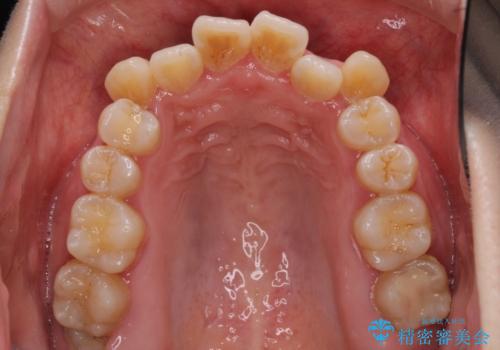

- 前歯がデコボコした上に口元が閉じにくいことを気にして来院された患者様です。

IPR(歯と歯の間を削る)と側方拡大では口の閉じにくさは改善できそうになく、一方で抜歯矯正を行うほどの突出感は認められませんでした。

親知らずを全て抜去し、歯列全体を後方に移動させることで口元の閉じにくさいを改善していくこととしました。